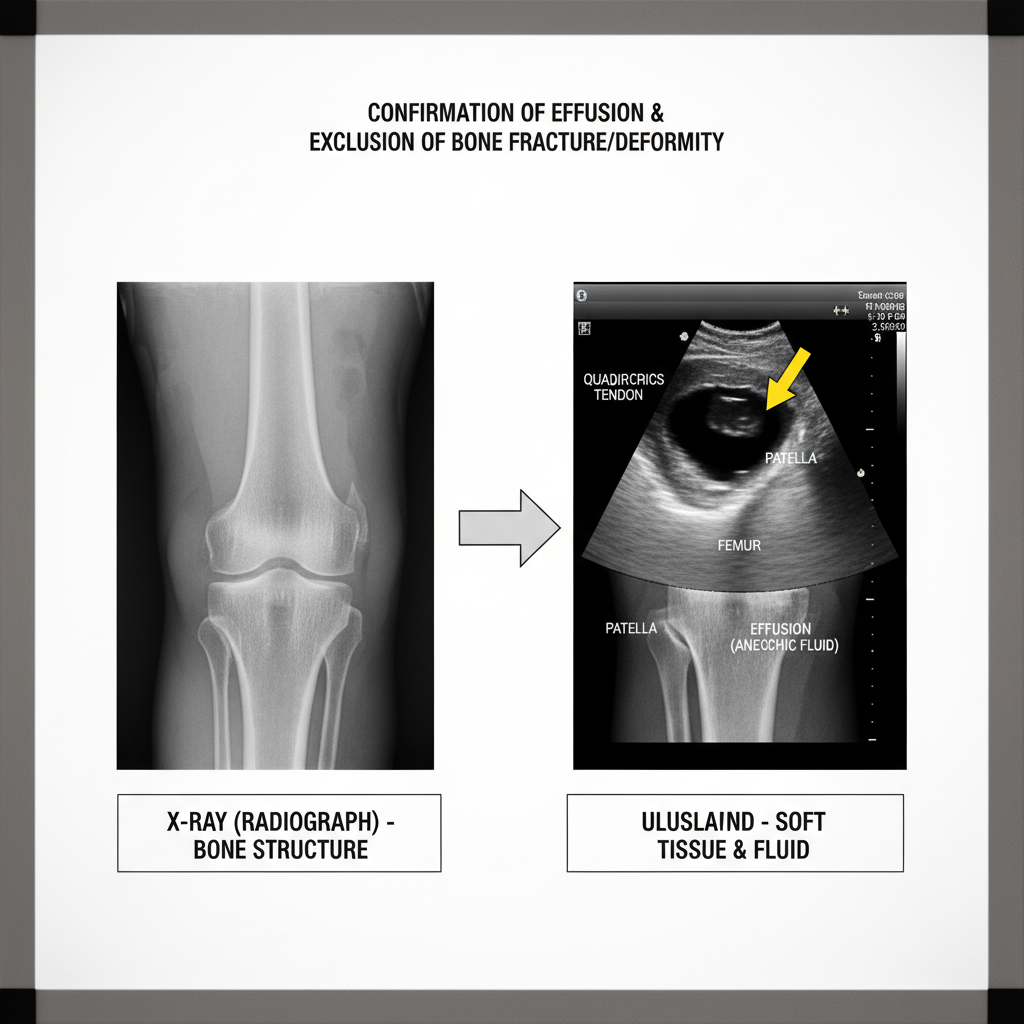

무릎에 찬 물을 주사기로 뽑는 것에 대해 거부감을 느끼시는 분들이 많습니다. 하지만 통증이 너무 심하고 부종이 심하다면 압력을 줄이기 위해 물을 뽑아내야 하며, 뽑아낸 액체의 색깔을 통해 정확한 원인을 진단할 수 있습니다.